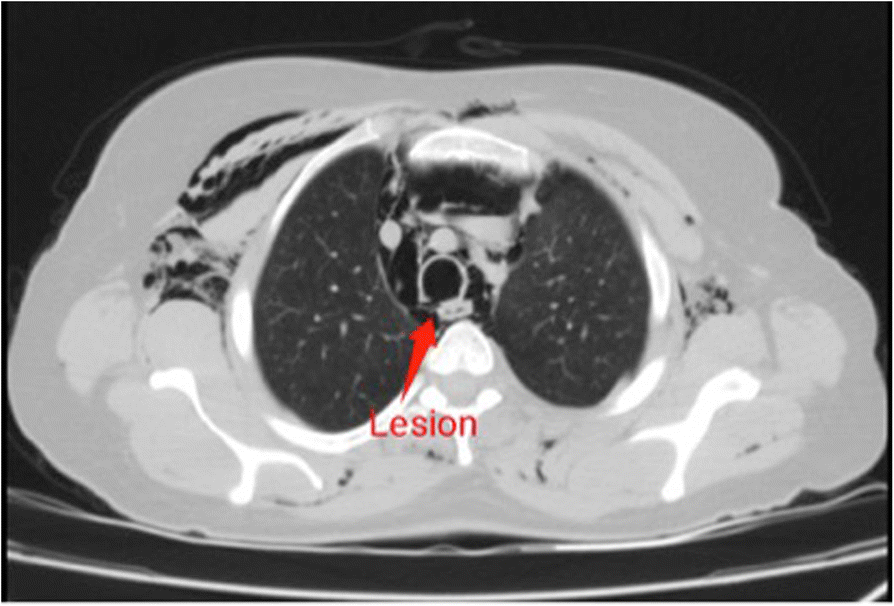

Thoracic CT showing posterior tracheal rupture (Arrow). Download Tracheal Rupture The major causes of tracheal injury include iatrogenic, blunt trauma, penetrating trauma, inhalation and aspiration of liquids or objects. Tracheobronchial tears are uncommon injuries or lacerations or puncture occurring anywhere in the tracheobronchial tree resulting from penetrating or blunt trauma to the neck or. Common etiologies include blunt or penetrating. A tracheal or bronchial rupture is a tear or break. Tracheal Rupture.